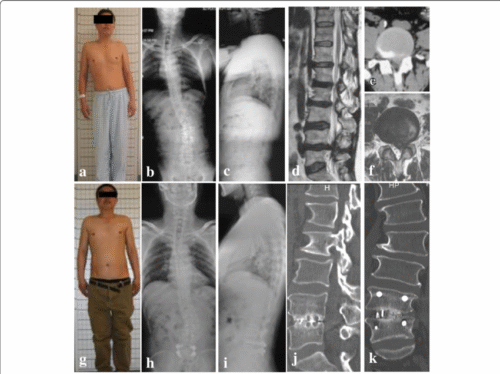

يبدأ هذا النوع منذ مرحلة الطفولة أو المراهقة ويستمر حتى البلوغ. بعد اكتمال نمو العظام، قد يتوقف تطور الانحناء، لكن مع تقدم العمر، يمكن أن يزداد الانحناء نتيجة تدهور الأقراص والغضاريف بين الفقرات. يعرف هذا النوع أحيانًا باسم الجنف التنكسي عند البالغين.الجنف التنكسي الجديد (De-Novo Scoliosis)

يظهر هذا النوع لأول مرة عند البالغين دون تاريخ سابق للجنف. يحدث غالبًا بسبب تآكل الغضاريف والمفاصل بين الفقرات، خاصة في المنطقة القطنية. في بعض الحالات، يصعب التمييز بينه وبين النوع الأول، خصوصًا إذا لم يتم تشخيص الانحناء في سن مبكرة.

الجنف عند البالغين قد يكون استمرارًا لحالة بدأت في الطفولة أو يظهر نتيجة التغيرات التنكسية في العمود الفقري. الاكتشاف المبكر والفحص المنزلي يمكن أن يساعد في التعرف على العلامات الأولية، لكن التشخيص الدقيق يتطلب تقييمًا طبيًا متخصصًا. من خلال المتابعة المستمرة، ممارسة التمارين العلاجية، والحفاظ على نمط حياة صحي، يمكن التحكم في الانحناء والحد من المضاعفات، مع الحفاظ على جودة الحياة والصحة العامة للعمود الفقري.